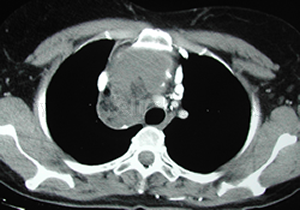

Angiosarcoma

Timoma |